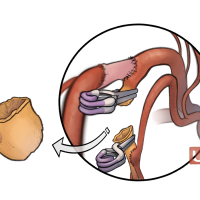

FEN2022シリーズ